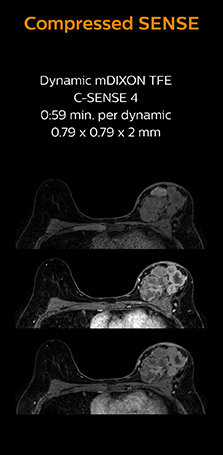

Cardiac MRI of acute myocardial infarction (AMI) w/wo Compressed SENSE

These images of a patient with acute myocardial infarction images were acquired on Ingenia 1.5T with and without Compressed SENSE.

3D whole heart MRI and coronary arteries w/wo Compressed SENSE

These images with and without Compressed SENSE were acquired on Ingenia 1.5T.

Faster1 cardiac imaging with fewer or shorter breath holds

Dr. Koshi Miyake, cardiologist, explains that scanning of patients with cardiac arrhythmia can be challenging, as scanning times can become very long due to the varying heart rate. So his most important motive to implement Compressed SENSE in cardiac MRI exams was to reduce the burden of breath holds for the patient, while maintaining high image quality. He hopes this can also help to reduce motion caused by the difficulty for patients to hold their breath.

“Compressed SENSE has now been implemented in all cardiac exams. Thanks to the acceleration, fewer breath holds are now needed, or breath hold times are shortened. This reduces the burden of the exam for cardiac patients, without affecting the quality of information required for cardiac function analyses,” he says. “Because it’s easier for patients to comply with the breath hold times”

“In our previous cardiac cine sequence, we were acquiring two slices during one breath hold. With Compressed SENSE, we increased this to four slices per breath hold. It is also possible to shorten scanning time using a C-SENSE factor 6 without sacrificing image quality.”

“Typically, in scans with high contrast, such as 2D balanced TFE cine, a quite high C-SENSE factor may be used. When we tried a higher C-SENSE factor, we saw still no significant influence on cardiac ejection fraction, but 2D image quality started to decline. For coronary imaging, we use a C-SENSE factor of 3 in 3D balanced TFE, or even up to 4 when contrast is high.”